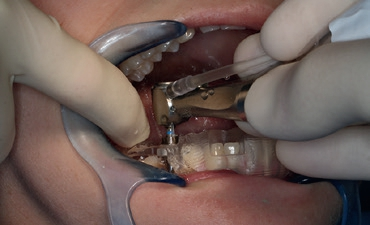

Nach der geführten Implantatbettaufbereitung wurde das Astra Tech Implant System EV 4,8C × 13 mm durch die Hülse hindurch mit Höhenanschlag in seine geplante Position inseriert (Eindrehmoment final: 45 Ncm) (Abb. 8 bis 10). Die Lage des Implantats wurde mit einer intraoralen Röntgenaufnahme postoperativ überprüft (Abb. 11). Es folgte die digitale Abformung mit der CEREC Omnicam: Um die Implantatposition exakt zu übertragen, wurde ein Scanbody platziert (Abb. 12). Der dabei erzeugte Scan wurde für das präzise Design eines Provisoriums mit der Abformung des Milchzahnes überlagert und im Anschluss gefräst (Abb. 13). Das Kunststoffprovisorium wurde mit der dazugehörigen TiBase verklebt (Multilink Hybrid Abutment, Ivoclar Vivadent). Zuvor wurden sowohl die TiBase als auch das Zirkonabutment sandgestrahlt, im Ultraschallbad gereinigt und im Anschluss silanisiert (Monobond plus, Ivoclar Vivadent). Im nächsten Schritt wurde das Provisorium mit dem Implantat okklusal verschraubt (Abb. 14) und mit Komposit verschlossen (Abb. 15 bis 17). Um eine Überbelastung des Implantats während der Einheilzeit zu vermeiden, war eine Nonokklusion von 0,5 bis 1 mm zum Antagonisten zu beachten. Dazu gehörte auch die Empfehlung an die Patientin, das Provisorium in den ersten Monaten nur eingeschränkt zu belasten (weiche Kost).